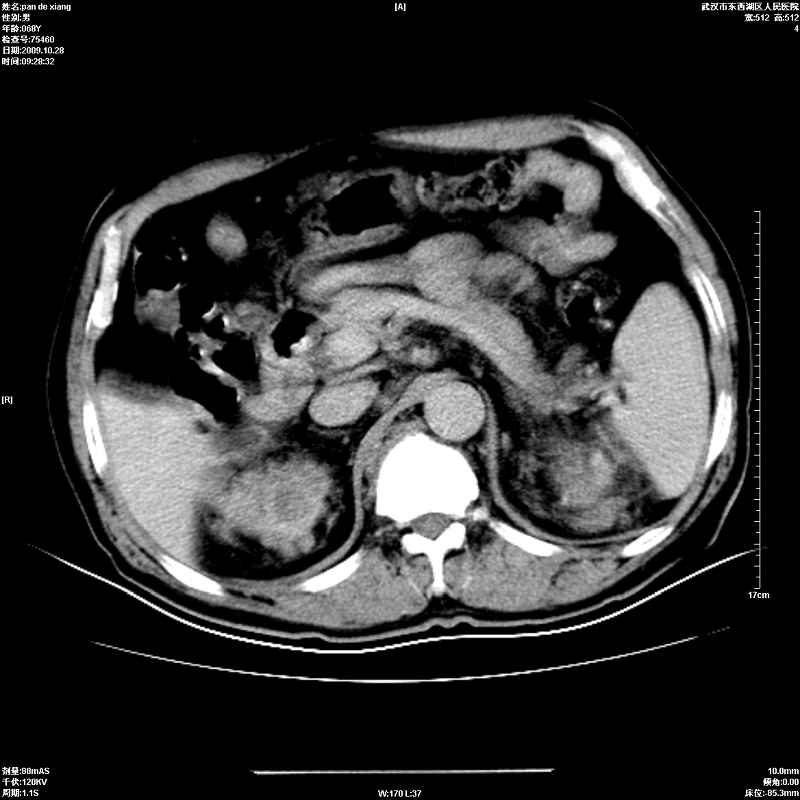

以下是引用杀毒软件在2009-10-28 20:41:00的发言:[br]结合临床考虑---白血病双肾改变或淋巴瘤。

以下是引用zxl51642在2009-10-29 9:59:00的发言:[br]结合临床“单克隆免疫球蛋白血症”,考虑双肾为继发损害并肾功能不全(尿中大量igg及少量iga、igm等大分子免疫球蛋白滤出所致继发损害),椎前软组织肿块为髓外造血。与浆细胞瘤有区别,平扫时有战友说的很清楚。